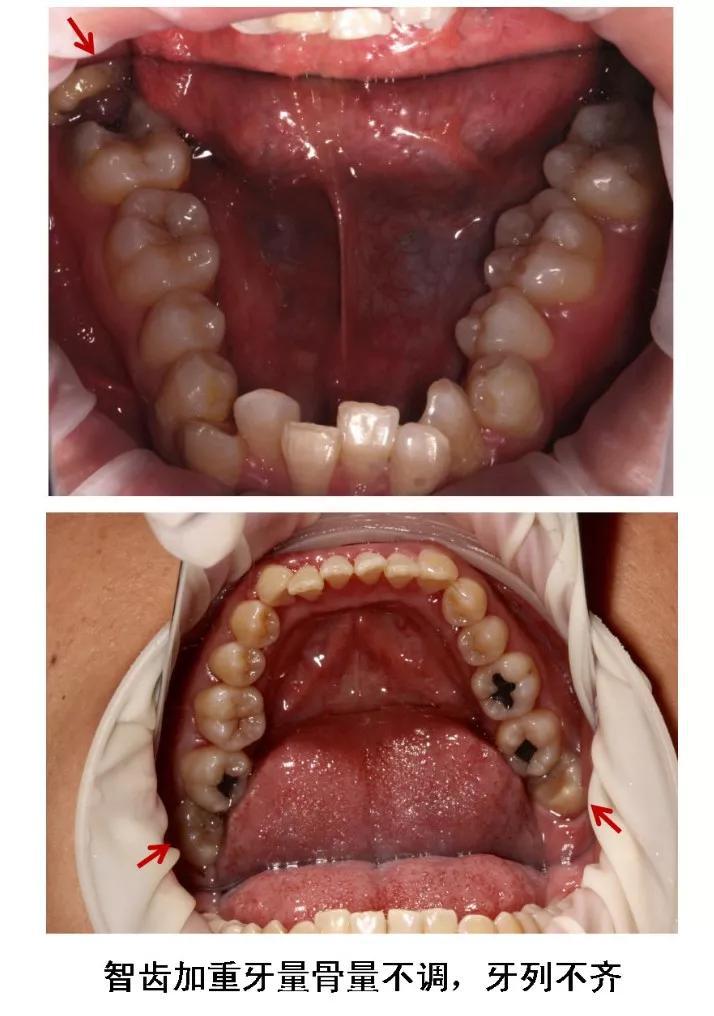

6、牙齿需要矫正,以及在12-16岁做过矫正的小朋友 ,需要根据正畸医生的建议,及时拔除智齿,以获得完美的牙列和脸型!